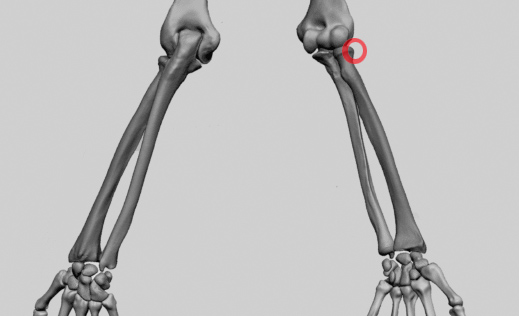

In der Nacht gehe ich vom Ehebett ins Wohnzimmer wo ich meine, den Arm besser lagern zu können. Aber an Schlafen ist nicht zu denken. Ich frühstücke, dusche noch mal und fahre Samstag den 13. Dezember 2025 mit einer Armbinde auf die Notfallambulanz. Hier fragt man mich, warum ich nicht gleich gekommen sei. Ich antworte, dass der Unfall am selben Tag passiert sei, halt kurz nach Mitternacht. Das hat jedoch nichts am später diagnostizierten Bruch geändert. In einem ersten Röntgen ist fast nichts im Ellbogen, der vorrangig schmerzt, zu erkennen. Der Aufnahmewinkel lässt anscheinend die Teile so erscheinen als wären sie gut beisammen, man sieht nur einen Schleier im Knochen. Ein zweites Röntgen bringt Klarkeit. Durch den Sturz landete das ganze Körpergewicht auf der rechten Hand. Diese hielt stand. Der Schlag setzte sich bis in den Ellbogen fort wo das sog. Radiusköpfchen brach. Der Radius ist die Speiche, also der obenliegende Knochen des Unterarms. Dieser endet im einer Hohlform die am Oberarmknochen über ein Köpfchen greift, dieses aber nicht umschliesst und bei starken Armverdrehungen sich aus “auskuppeln” kann (im Gegensatz zur besser verankerten Elle). Anscheinend war dies beim Sturz der Fall und die Halbholform traf nicht genau auf das Köpfchen gegenüber. Ein Teil der Halbholform brach aus und verschob sich über 2 Millimeter nach hinten.

Diesen Versatz sah man dann im zweiten Röntgen, welches mit 45 Grad in den Ellbogen aufgenommen wurde. Der Spalt war grösser als 2 Millimeter, aber nur knapp. Das nennt man fachlich Radiuskopffraktur rechts Mason Typ II. An dieser Grenze wird entschieden ob man eine konservative Verheilung anstrebt oder ob operiert werden muss. Über 2 Millimeter muss normalerweise operiert werden aber es gibt nur um eine par Bruchteile Millimeter darüber. In der Notfallambulanz der Klinik Innsbruck will man die Entscheidung der Handambulanz überlassen und man verpasst mir einen Spaltgips von der Hand bis zur Schulter über den Rest des Wochenendes. Der Spalt bedeutet nicht dass er abnehmbar ist, er ist bloss ein wenig leichter. Ich war ganze 6 Stunden dort. Aber auch mühsam verletzte (Schulterbruch) liess man so lange warten.